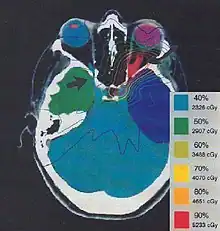

Most ophthalmologists will not advocate any treatment unless visual loss is present and ongoing. Reports of patients with ONSM having no change in their vision for multiple years are not uncommon. If loss of vision occurs, radiation therapy will improve vision in about ⅓ of cases, and preserve vision in about ⅓ of cases. Surgery has traditionally been associated with rapid deteroriation of vision. However, newer surgical techniques may prove better for the treatment of ONSM.[4][6][7]